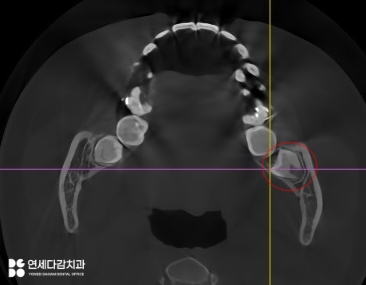

가락동 치과 에서 설명하는 케이스는

교합면이 혀쪽으로 향해 있으며,

진료 접근을 위해서는 잇몸 절개 후

골 삭제가 필요할 것으로 판단됩니다.

더불어, 아래쪽 매복 어금니 같은 경우

치근단 하방 하치조신경관과 근접할 때가 많아

사전에 정확한 거리 관계를 파악합니다.

따라서 안전한 각도와 접근 경로를

충분히 고려한 진료 계획 수립이 필수입니다.